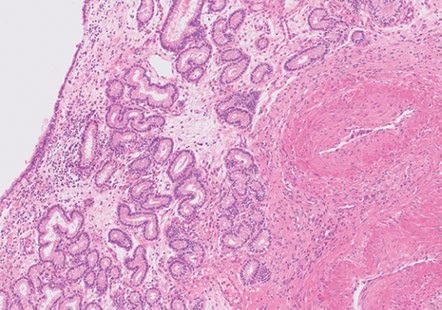

Mammary Glands I. Indications for biopsy/pathological evaluation Mammary lesions are among the most common samples…